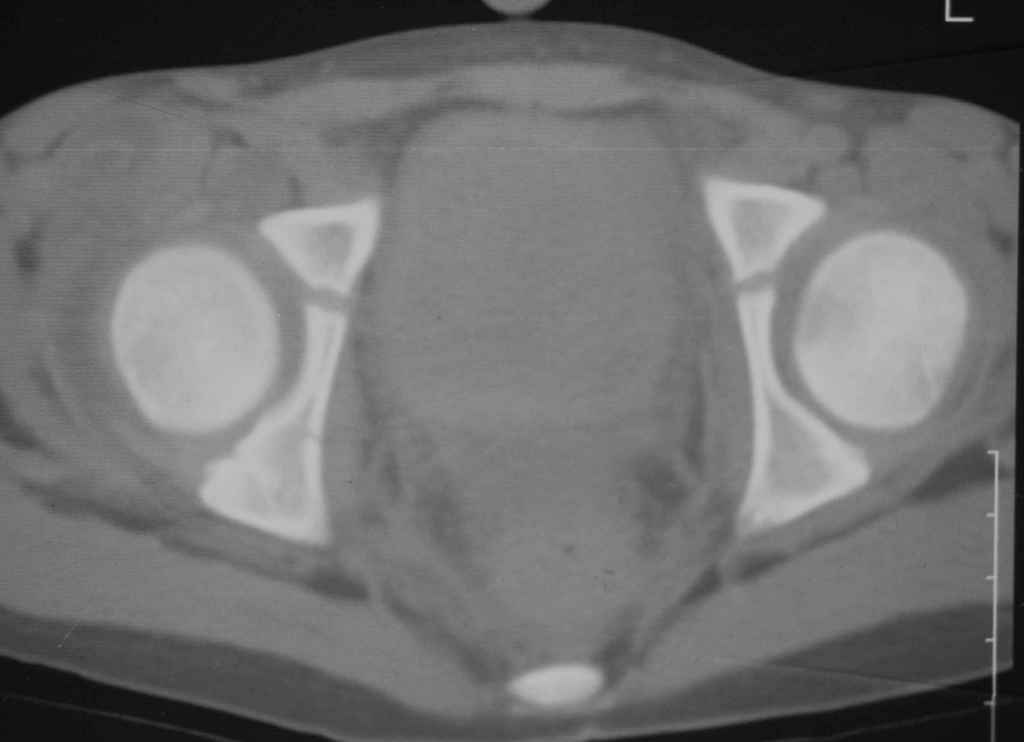

Уважаемые коллеги, помогите определиться с тактикой лечения. Ребёнок 7 лет, травма 11.09.08, поступил с травматическим вывихом бедренной кости.

Вывих вправлен, конечность фиксирована на скелетном вытяжении. Что делать с переломом подвздошной кости? Лечить консерватино или оперировать?